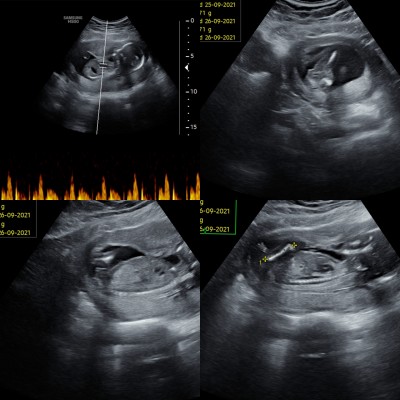

kızlar doktorum birsürü resim verdi ama hangisi bebegimin bacak arası ya anlayamadim

En alttaki. Popodon almış resmi bacaklar yukarıda. Sanırım kız öyle mi Allah bağışlasın

Sanırım en sonda ki bacak arası diğerleri uzuv ölçümleri cunki be cinsiyeyode kız gibi canım eger o bacak arasında ")

En üstte bacak arasında çıkıntı var kordon olabilir. En altta da bacak aradı boş. Büyük ihtimalle kız